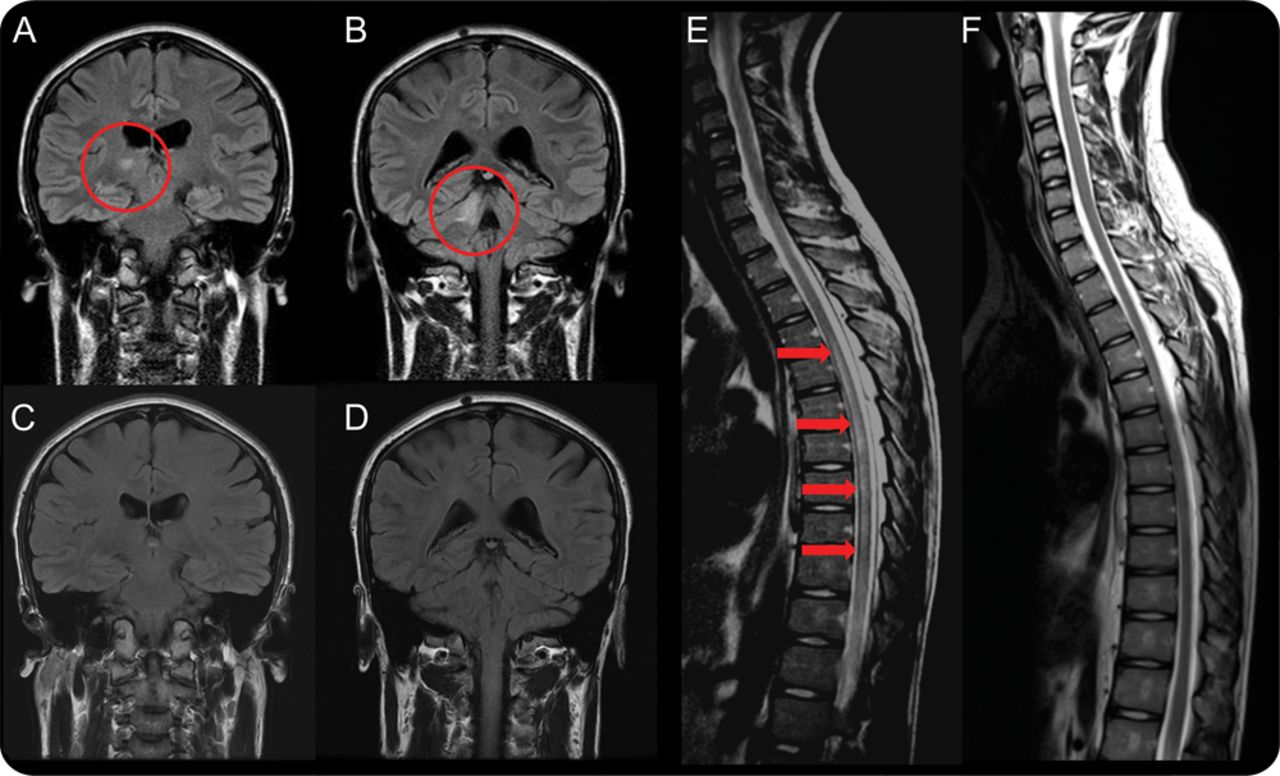

三个4 MOG-Ab-positive患者男性,在3和TM同时或顺序发生,和临床恢复非常好。此外,MRI异常解决完全在3/3病人后续成像和诱发电位规范化评估(图2)。此外,没有病人随后复发,虽然免疫抑制治疗已撤回1和大幅锥形3。相比之下,AQP4-Ab-positive动/ NMOSD是女性主导,4的全部综合症和TM在出现异常,4我们发现在我们的病人,relapse-related残疾是常见的。14在我们的经验中,诱发电位通常倾向于保持异常和脊髓成像显示持续异常信号变化和萎缩。因此,我们的研究结果表明,在成人MOG-Abs显然可能会发现在一个单相Devic-like表型,或许表明重叠ADEM的这个条件。

(模拟)冠fluid-attenuated反转恢复大脑MRI在急性疾病患者3显示T2 hyperintensity正确的丘脑(A)和小脑半球(B),与分辨率的变化1年后(C, D)。(E, F) T2 hyperintensity从T4/5 T11在急性疾病患者4 (E),完全损伤决议在10个月随访(F)。